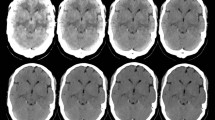

The proposed acquisition and processing protocols were those routinely used at each participating center with additional triple energy window (TEW) scatter correction (SC) and computed tomography (CT) based attenuation correction (CTAC). A multicenter phantom study was conducted on six imaging systems in five centers, with either single photon emission computed tomography (SPECT) or SPECT/CT, and two brain phantoms. The gray/white matter I-123 activity ratio in the brain phantoms was 4, and they were enclosed in either an artificial adult male skull, 1300 Hounsfield units (HU), a female skull, 850 HU, or an acrylic cover. The cut-off frequency of the Butterworth filters was adjusted so that the spatial resolution was unified to a 17.9 mm full width at half maximum (FWHM), that of the lowest resolution system. The gray-to-white matter count ratios were measured from SPECT images and compared with the actual activity ratio. In addition, mean, standard deviation and coefficient of variation images were calculated after normalization and anatomical standardization to evaluate the variability of the NDB.